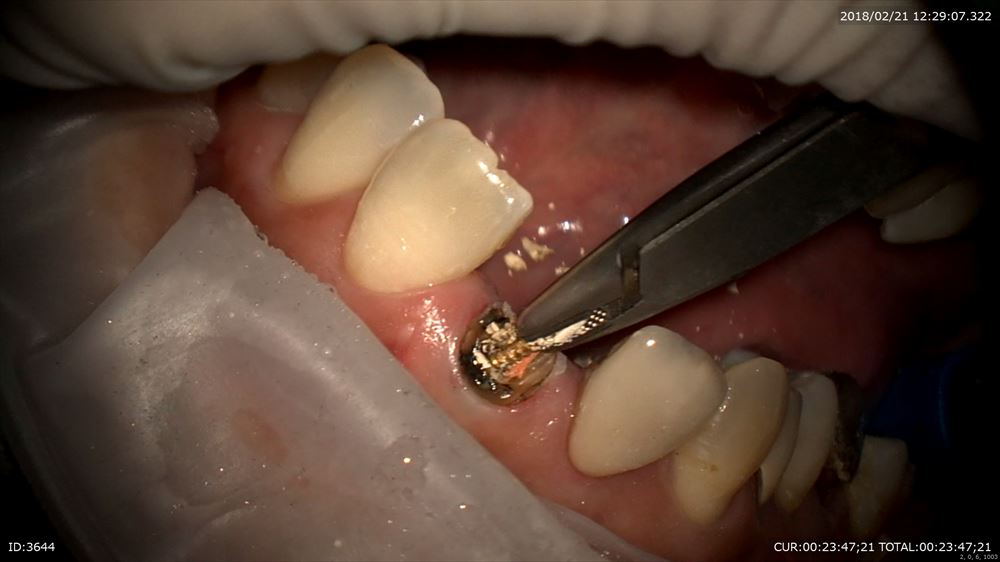

次の方は

「他院で説明がなくやっつけ仕事をされた」で来院

歯科ドックの後1.5時間カウンセリングでご納得いただき、

まず前歯から他院で折れているから抜かなければいけないかもとの事。外すと虫歯だらけ。。

確かに亀裂が!!

これを丁寧に除去(マイクロスコープだから安心!)

仮歯を作り

今日は終了

この歯も保存できます。お口全体にトラブルがありますのでカウンセリングでお話しした通り進めていきます。笑顔で帰られて良かった!!